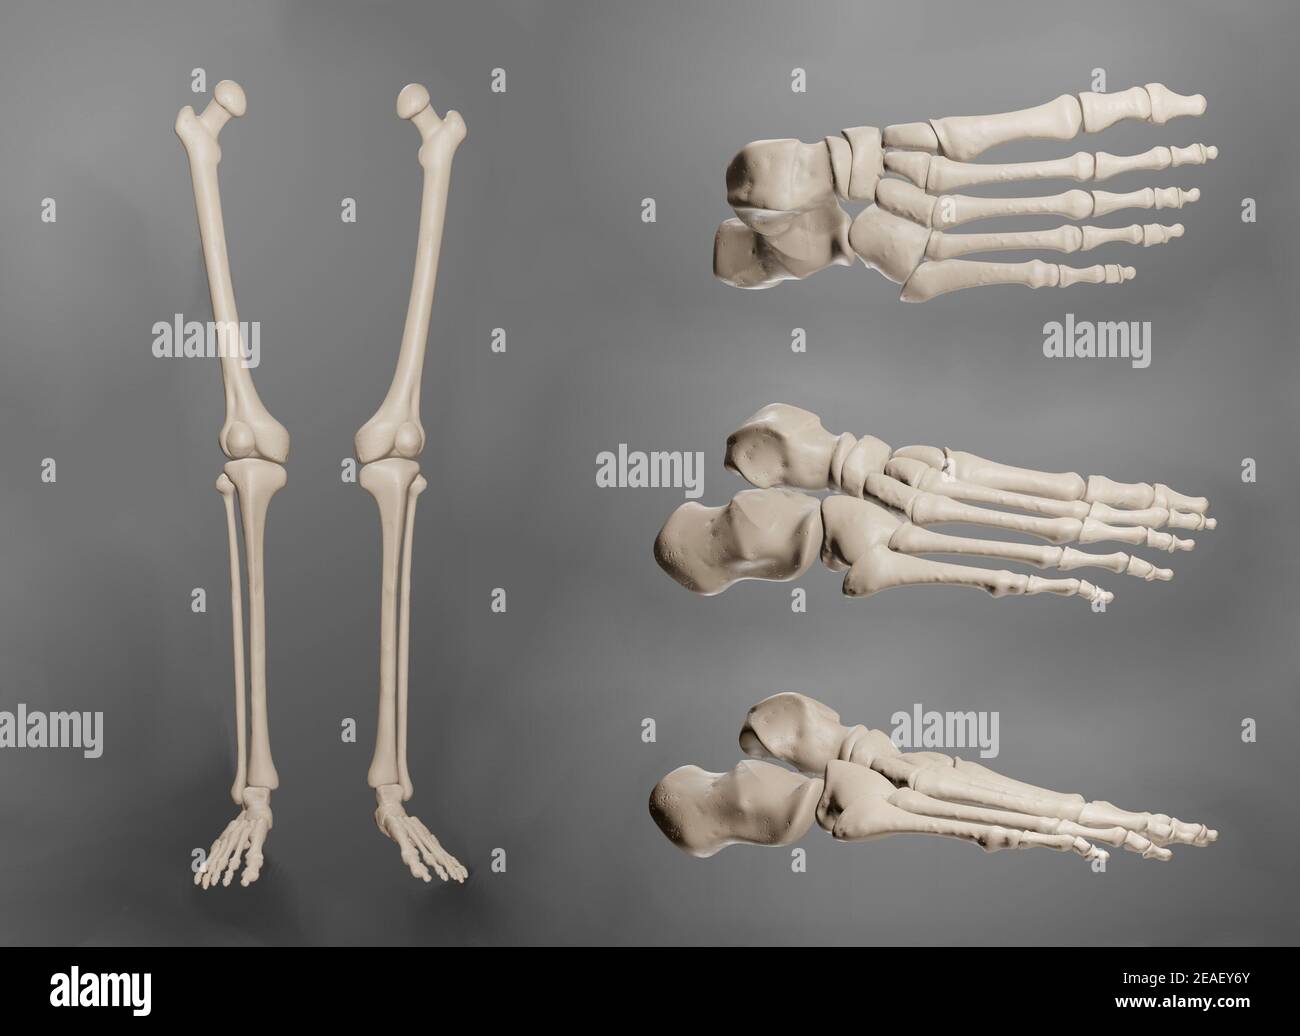

RF2K3D0JR–OS précis des os du pied gauche humain ou squelette 3D illustration du rendu. Vues latérales, médiales, dorsales et plantaires. Anatomie, ostéologie, squelette

RF2DHMD0H–OS du pied. Anatomie humaine. Le schéma montre l'emplacement et le nom de tous les os du pied.

RMK228DY–Partie terminale du membre inférieur, reposant sur le sol au cours de posture droite ; le squelette du pied a 26 os.

RMK227XM–Partie terminale du membre inférieur, reposant sur le sol au cours de posture droite ; le squelette du pied a 26 os.